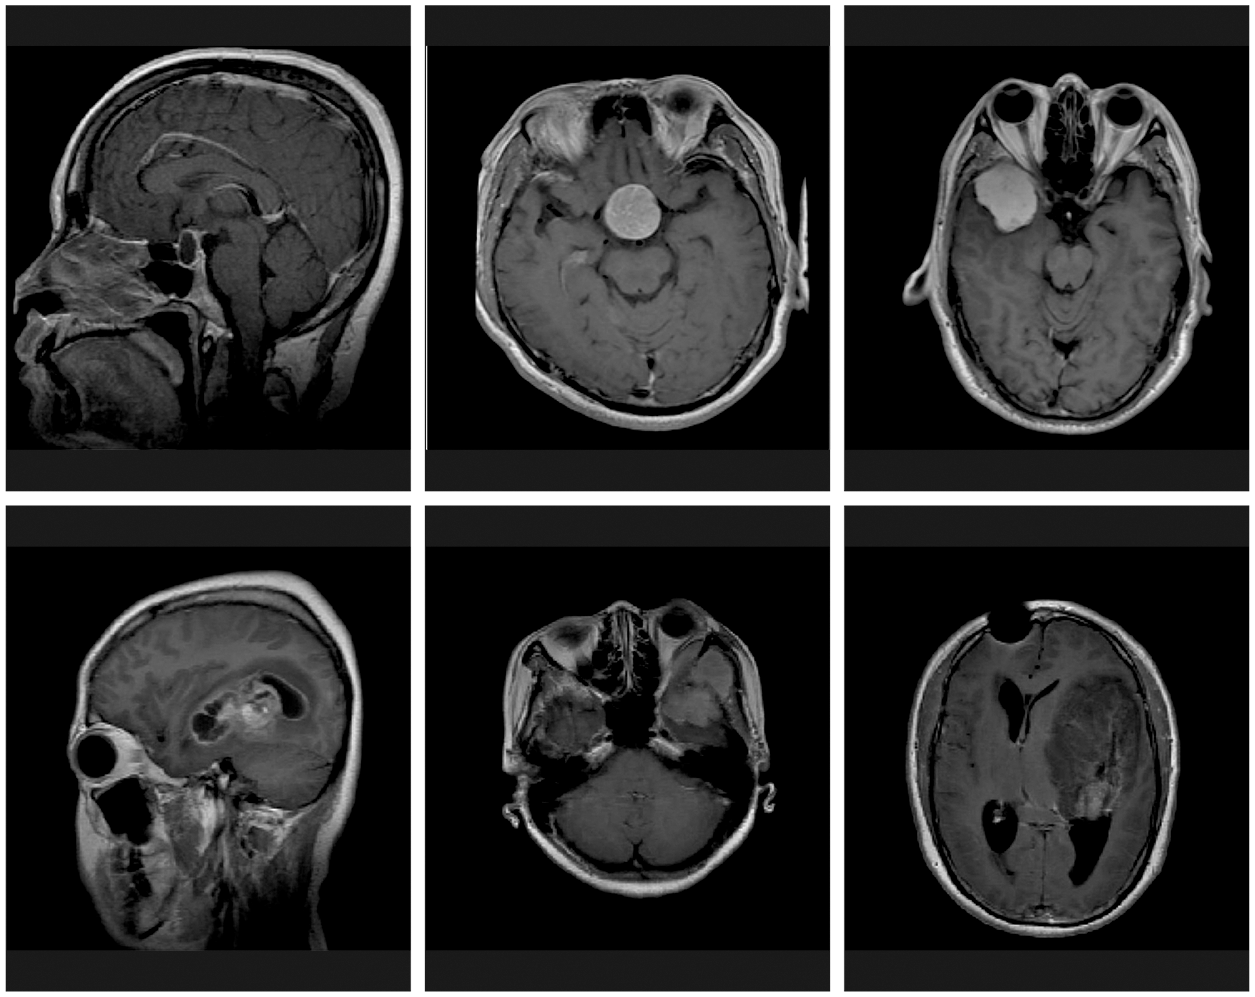

The performance validation of the HGSO-FHDF technique is tested using the Figshare dataset [21]. The dataset includes three class labels with 150 images under Meningioma, 150 images under Glioma, and 150 images under Pituitary classes. Fig. 3 demonstrates the sample set of test images.

Figure 3: Sample images